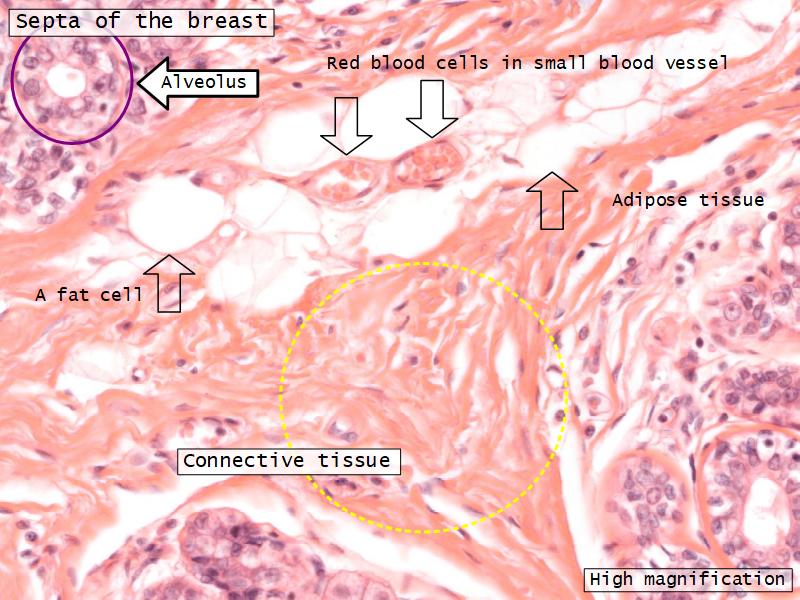

Mammary gland

Write short notes describing the structure of the mammary gland.

(5)

Mammary gland

- Compound tubuloalveolar gland

- 12 - 20 glands

- Each with own lactiferous duct

- Each with own lactiferous sinus

- Opens on skin at apex of nipple

Two stages

- Resting

- Active

Resting and active

Describe the resting mammary gland and compare with the active gland.

(8)

Resting gland

- Connective tissue dominate

- More adipose tissue

- Glandular tissue reduced

Active gland

- Terminal ducts expand

- Forms alveoli

- Connective tissue reduced

- Adipose tissue reduced

- Glandular tissue dominate

Structures

List the structures and cells found in the mammary gland.

Structures

- Lactiferous sinuses

- Stratified squamous near opening on skin

- Stratified cuboidal other parts

- Lactiferous ducts

- Stratified cuboidal

- Myoepithelial cells

- Underlie lactiferous ducts in most areas

- Basal lamina

- Separate epithelial components from stroma

Active gland

- Much larger than resting phase

- Terminal ducts proliferate to form alveoli

- Alveoli

- Surrounded by incomplete myoepithelial cells

Alveolar cells

- Apocrine secretion

- Active state

- Resting state